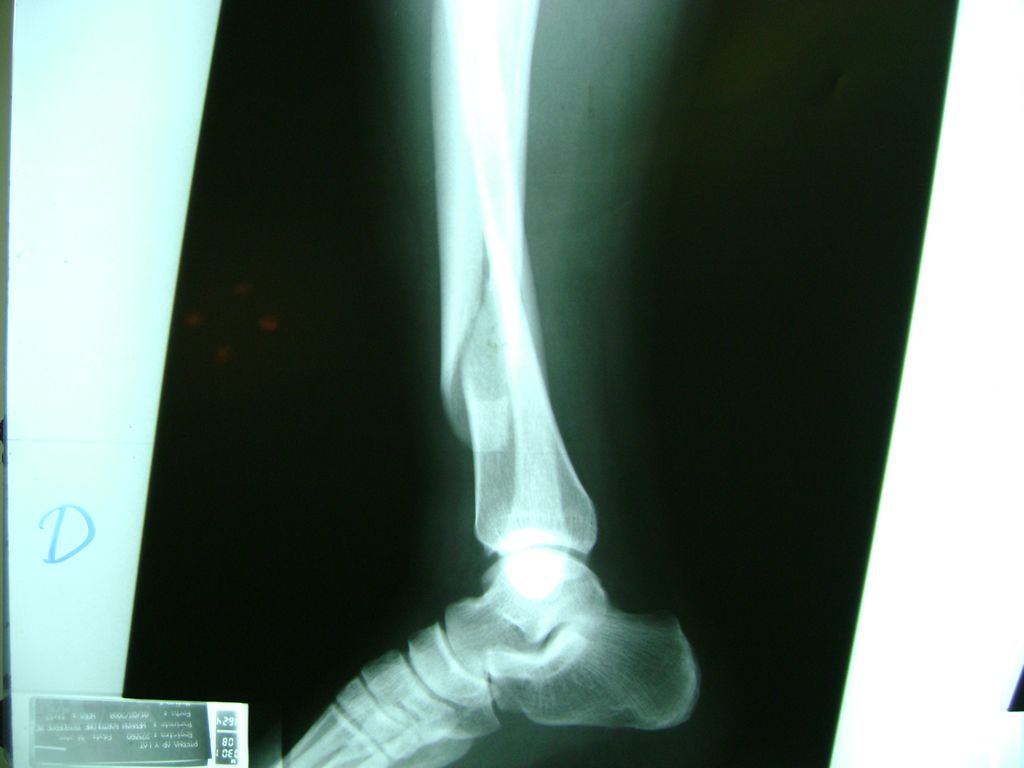

Húmero - Perone y Tibia

La mayor parte de las roturas implican a la parte proximal del hueso (parte del hueso próximo a la rodilla) o a la parte distal (parte del hueso cerca del tobillo).

Debido a la fina cobertura de piel que recubre la tibia y el peroné, las fracturas generalmente son abiertas, es decir, el hueso roto rasga la piel, atravesándola. Las fracturas de tibia y peroné generalmente se producen por un fuerte impacto o torsión.